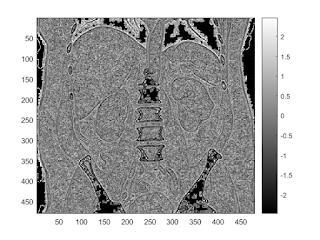

skew filter

f = @(X) skewness(X(:)); I2 = nlfilter(I, [3,3], f); imagesc(I2); colorbar;